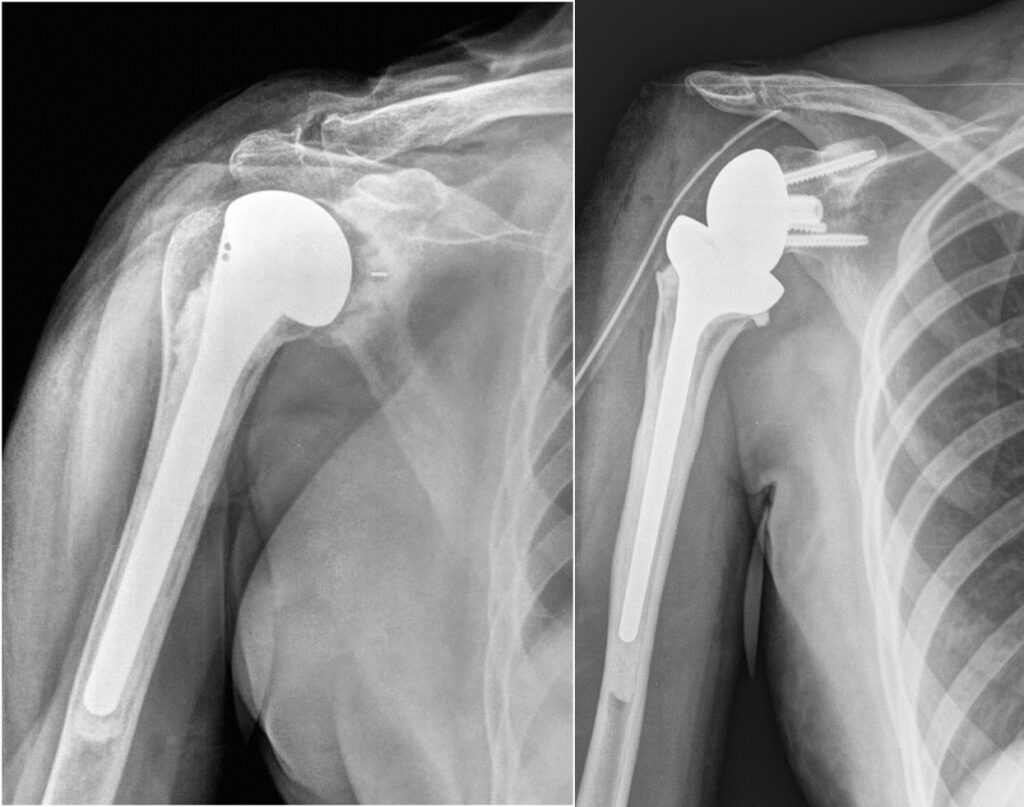

Эндопротезирование сустава – это полная замена поврежденного сустава искусственным протезом. Оно показано при выраженном, распространенном остеоартрозе с тотальным разрушением суставных поверхностей, когда другие методы лечения неэффективны, а боль значительно ограничивает качество жизни. ЭПС чаще рекомендуется пациентам старшего возраста. Преимуществами эндопротезирования являются быстрое и предсказуемое избавление от боли, более короткий период восстановления до полной нагрузки и высокая вероятность достижения стабильного функционального результата. Недостатки включают необходимость использования искусственного материала, риск износа протеза с течением времени и возможность специфических осложнений, связанных с имплантатом.

Эндопротезирование плечевого сустава для возвращения к активной жизни

Боль в плече и скованность движений мешают жить полноценно. Наша статья поможет понять все об операции по эндопротезированию плечевого сустава: от показаний и видов протезов до этапов восстановления и возвращения к любимым делам.